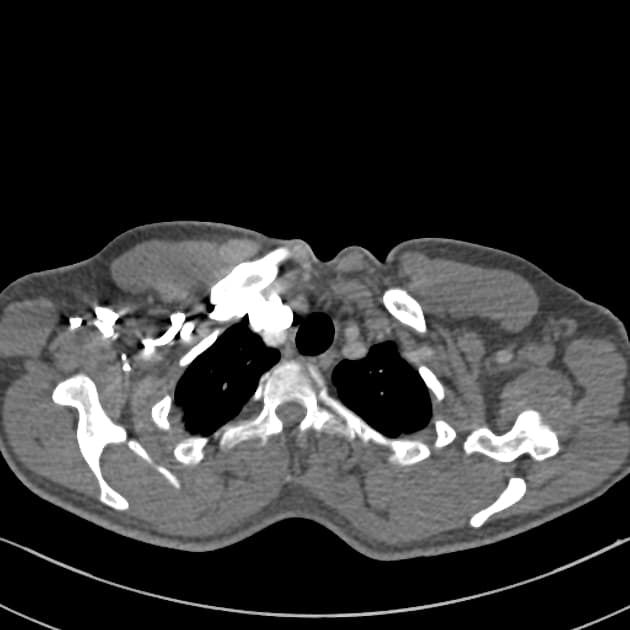

- Thấy vạt bóc tách (flap) trong động mạch chủ (aorta), xuất phát ở đoạn động mạch chủ lên (ascending aorta) ngay phía dưới gốc động mạch chủ (aortic root), xoắn dọc theo toàn bộ động mạch chủ (aorta), tạo thành buồng giả (false lumen) lớn nằm chủ yếu phía sau và chèn ép buồng thật (true lumen), buồng thật có hình bầu dục trên mặt cắt ngang.

- Thấy các cửa sổ thông (fenestration) tại đoạn cung động mạch chủ (aortic arch) gần đoạn gần và ngay trước phân nhánh động mạch chủ (aortic bifurcation).

- Toàn bộ động mạch chủ (aorta) giãn, đường kính lớn nhất tại đoạn động mạch chủ xuống ngực (descending thoracic aorta) đo được 5,1 cm.

- Buồng giả (false lumen) có hiện tượng huyết khối thành mạch (mural thrombus) một phần, không đồng đều, dày nhất ở đoạn động mạch chủ xuống ngực (descending thoracic aorta), làm giảm đường kính lòng mạch khoảng 50%.

- Điểm hẹp nhất của buồng thật (true lumen) nằm ở mức lỗ cơ hoành (diaphragmatic hiatus), đo được 2,9 x 1 cm.